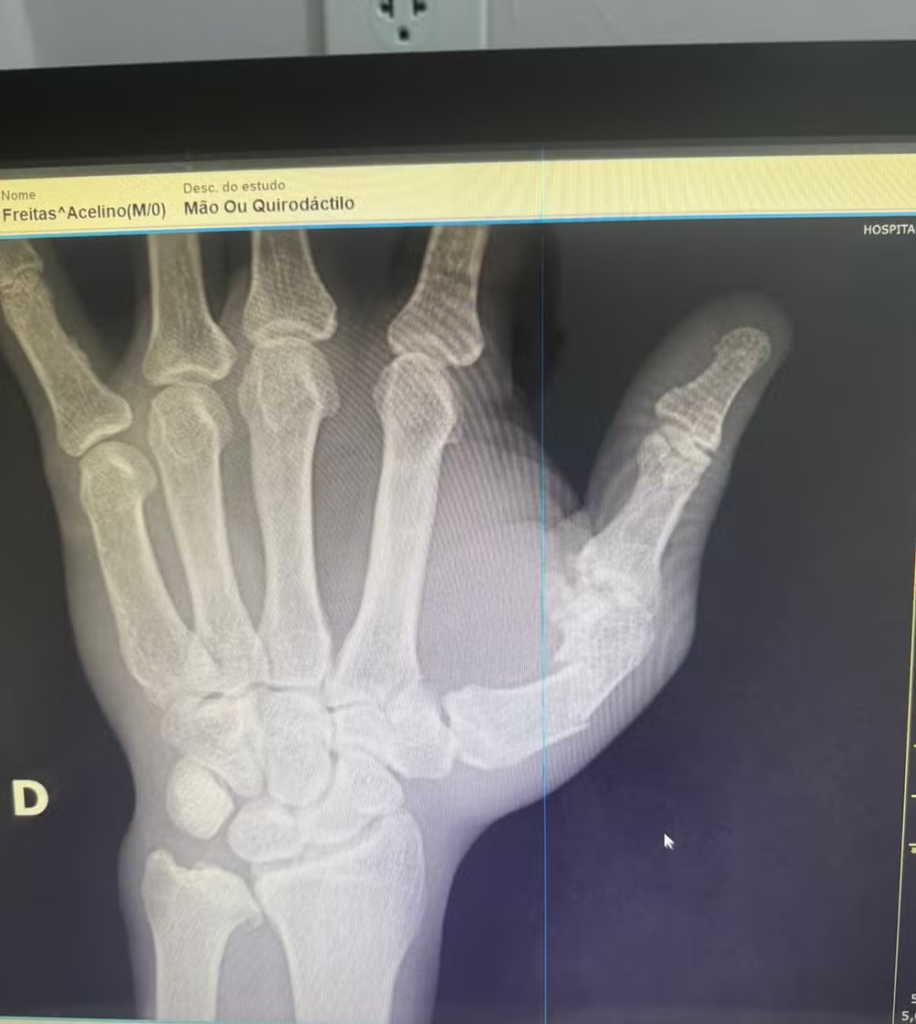

O que deveria ser uma noite focada na técnica e no desempenho esportivo se transformou em uma briga generalizada entre as equipes dos dois lutadores. Segundo informações da assessoria de imprensa de Popó, o lutador sofreu um machucado inusitado em sua carreira de 35 anos: uma fratura na mão esquerda, ocasionada durante a confusão. Este incidente levou Popó a passar por uma cirurgia em Salvador, cidade onde reside, e onde retornou logo após o evento tumultuado. A operação teve início ao meio-dia e estava programada para durar cerca de duas horas e meia, com o objetivo de reparar o dano causado na mão do lutador.